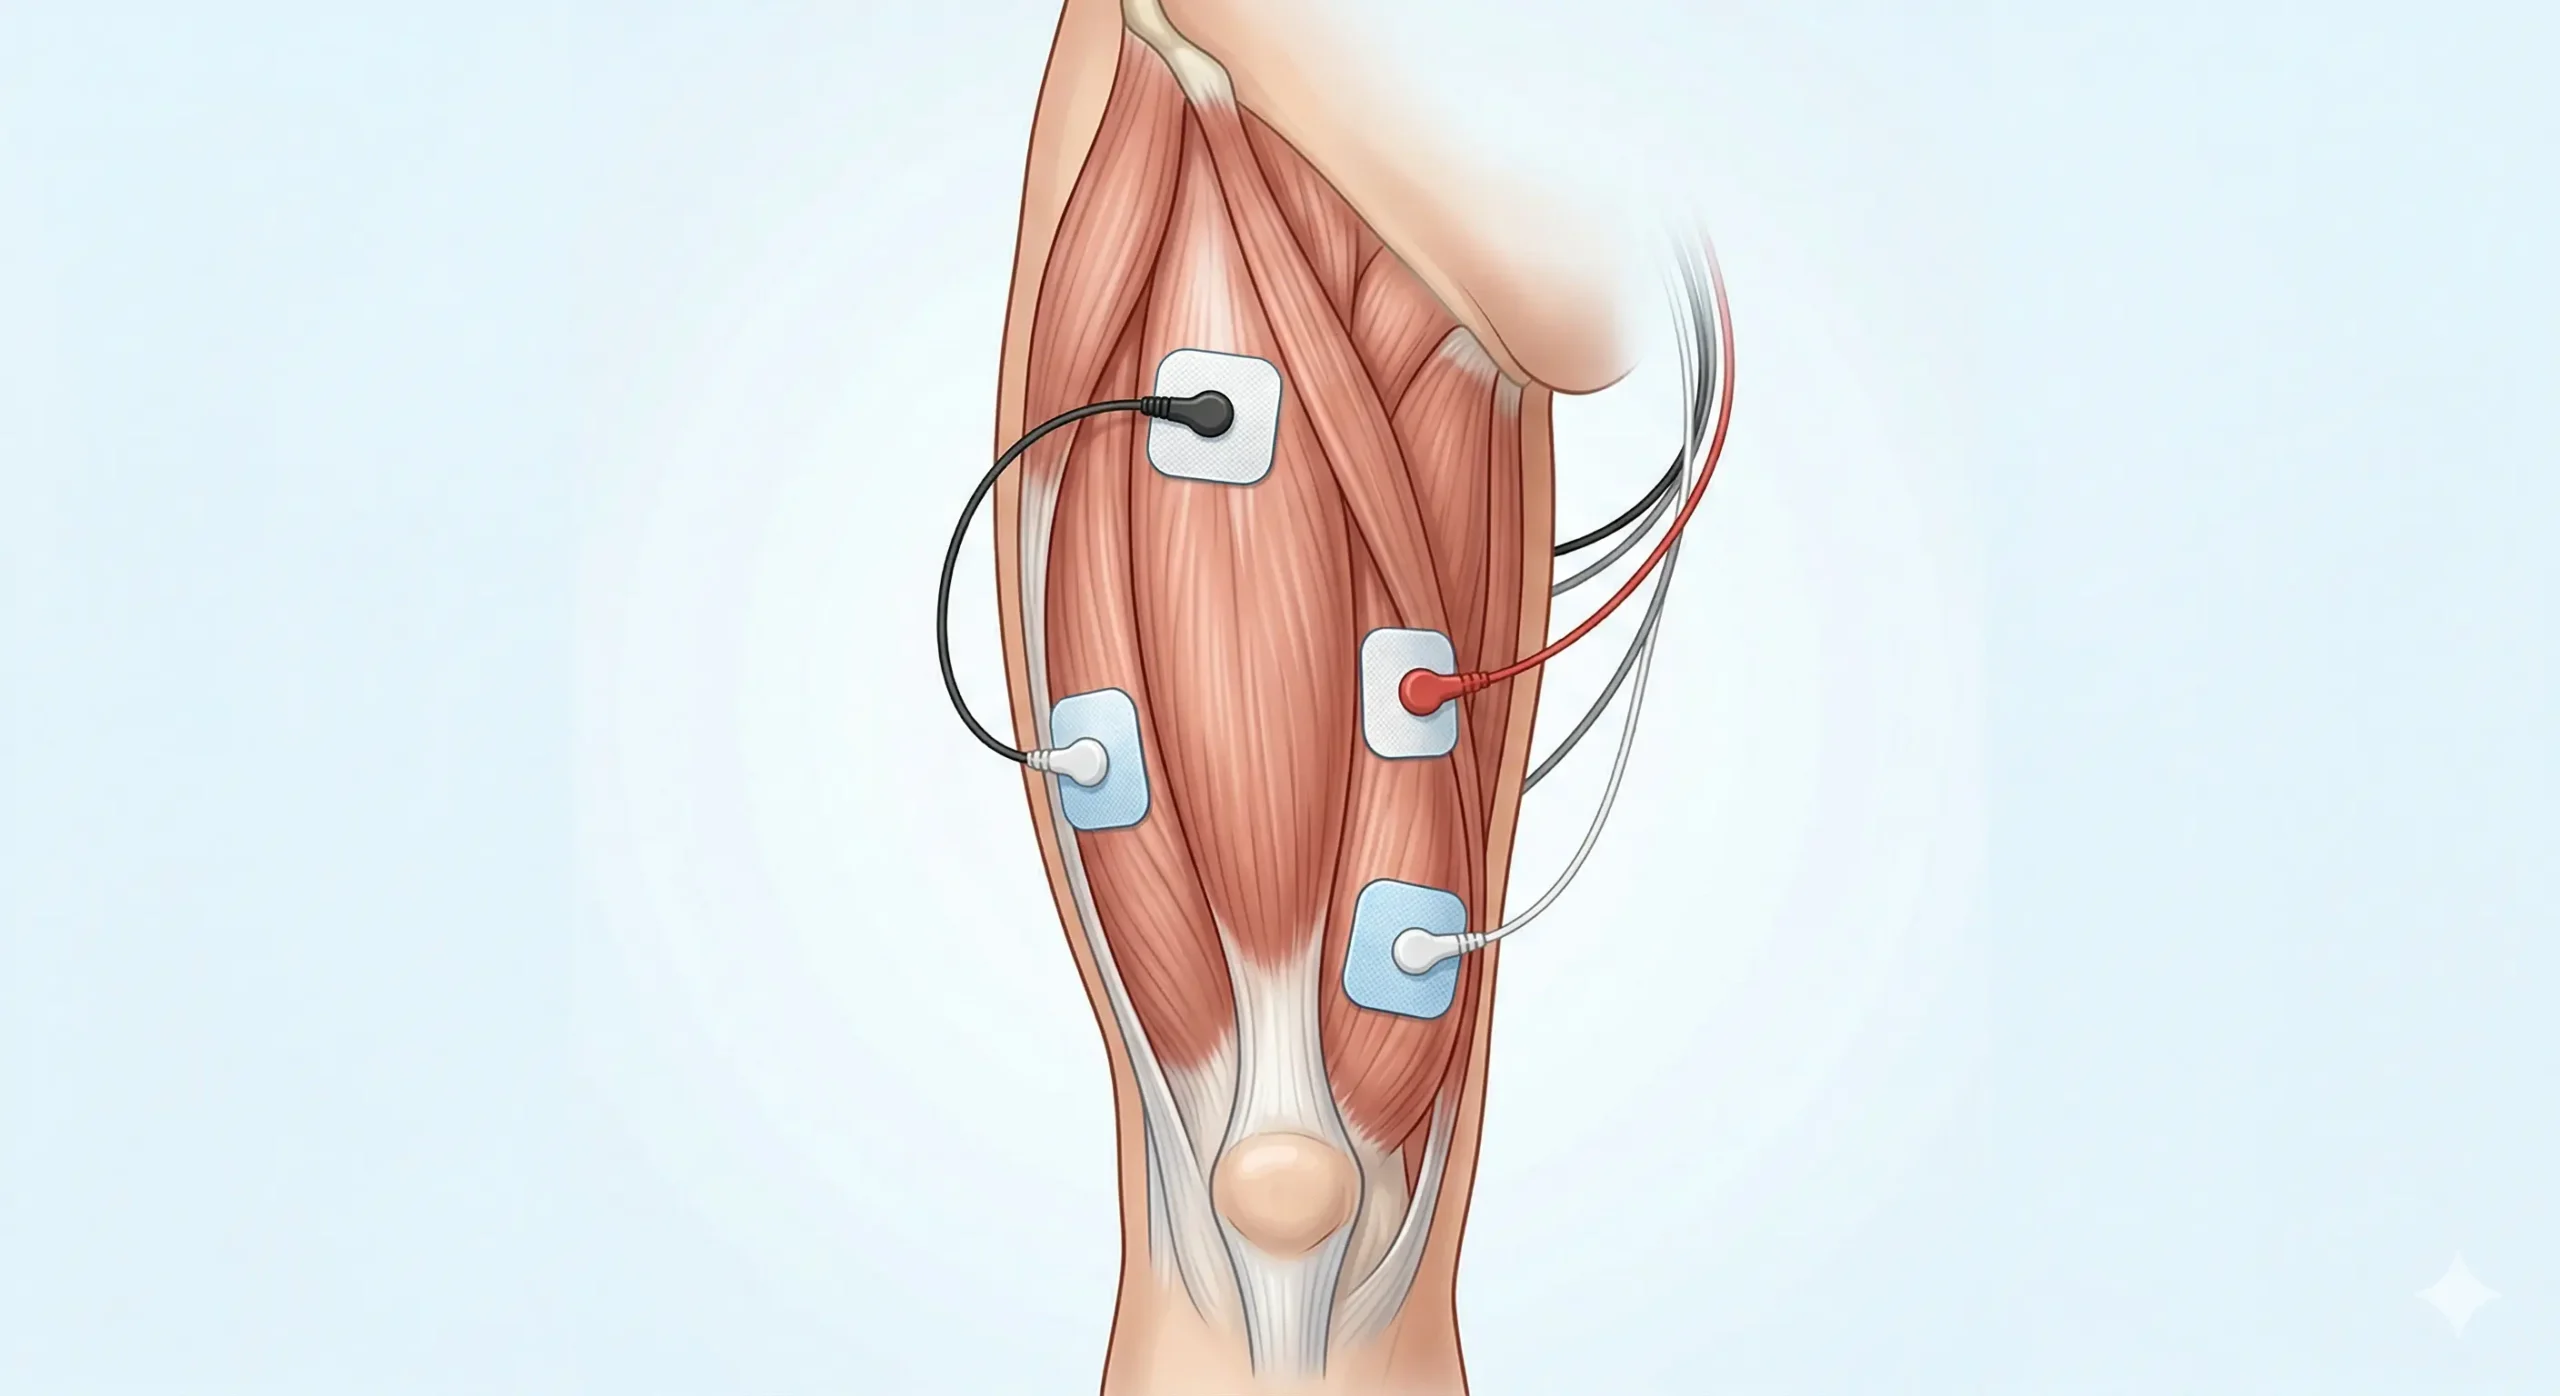

B) Imagen: TENS en vasto medial

Este montaje es más adecuado si la molestia está en la zona interna del muslo anterior. No coloques los electrodos directamente sobre la rótula.

TENS en vasto medial: cuándo desplazar los electrodos hacia dentro

El vasto medial está en la parte interna del cuádriceps y suele relacionarse con molestias en la zona interna-baja del muslo anterior. Para TENS no necesitas buscar una contracción específica del vasto medial; el objetivo es modular dolor o molestia, no aislar el músculo como en un entrenamiento EMS.